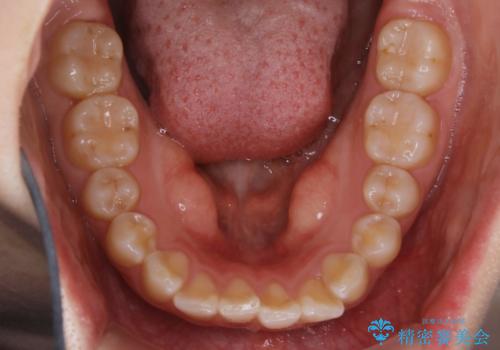

【非抜歯】ガタつきと歯軸を正して長持ちする歯へ

- 歯のガタつきと噛み合わせの改善を主訴に来院されました。

非抜歯で、少量の奥歯の移動と歯列の拡大・IPRを駆使して主訴を改善するための治療計画を立案しました。